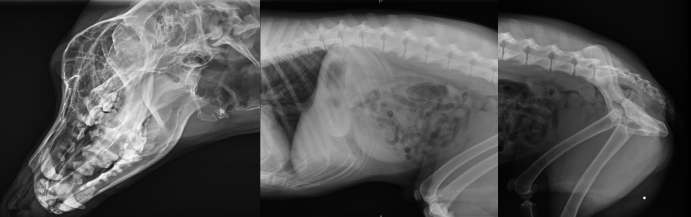

寵物DR片